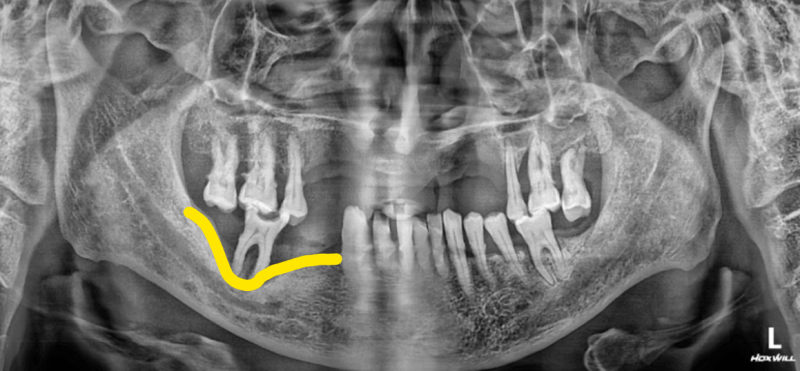

반갑습니다. 치의학 박사 장영준입니다. 임플란트 수술을 앞둔 분이라면, ‘뼈이식’이라는 단어를 한 번쯤은 들어보셨을 것이라고 생각됩니다. 뼈이식은 쉽게 말해 임플란트 픽스쳐(나사)를 심을 때, 잇몸뼈를 더욱 단단하게 보충하기